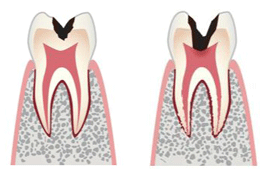

歯髄温存療法

進行度がC2でも、C3に近い段階まで進んでいる場合、歯髄が炎症を起こしていることがあり、 歯髄を除去する治療である「抜髄(ばつずい)」が行われます。

しかし、象牙箕が薄く残っているなら、「歯髄温存療法」により、歯髄を残せる可能性があります。

これは、むし歯を全部削ってしまうと、歯髄が露出してしまいそうな時にとられる」方法です。歯髄が露出すると感染しやすくなるので、あっという間にC3に進む可能性があるからです。

それを避けるために、あえてむし歯を少し残し、象牙質の増殖を促す水酸化カルシウムなどの薬を塗布して、 セメント剤などでふたをします。後日ふたを取り、象牙質が十分に増殖していたら、レジン修復を行います。

象牙質の増殖が不十分な時は、もう一度、薬を塗布してふたをします。

治療期間は長くなりますが、うまくいけば、進行したC2のむし歯がレジン修復で治りますから、メリットは大きいです。